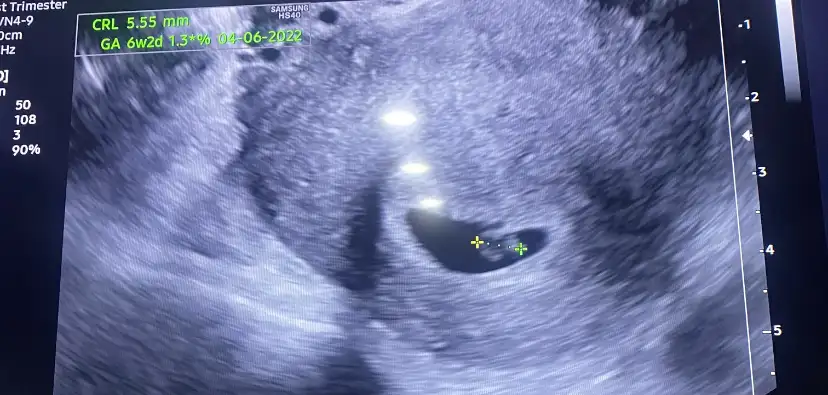

ben kontrolden çıktım, ikili test için kan alındı, sonuçları iki gün içinde çıkar denildi, detaylı kontrolde de ensesini vs ölçtüler, her şey yolundaymış, kan sonucu da çıkınca arayacaklar